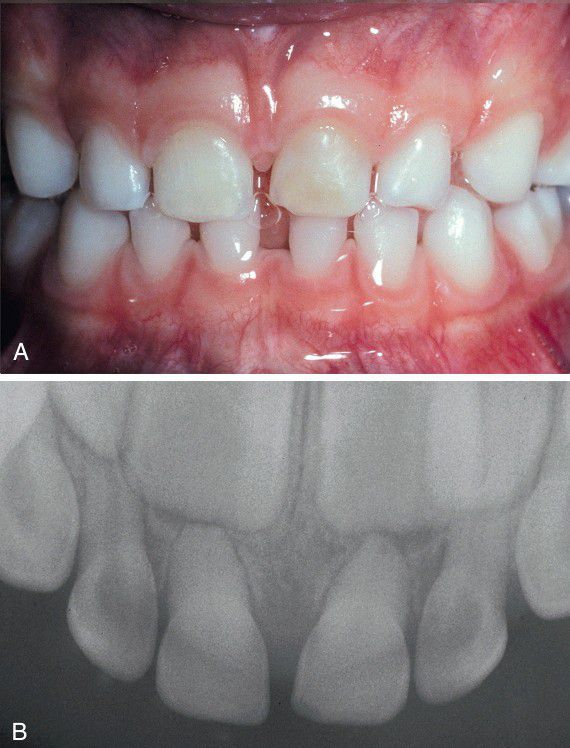

Calcific Metamorphosis.

A, Left deciduous maxillary central incisor exhibiting yellow discoloration. B, Radiograph of the same patient showing total calcification of the pulp chambers and canals of the deciduous maxillary incisors.